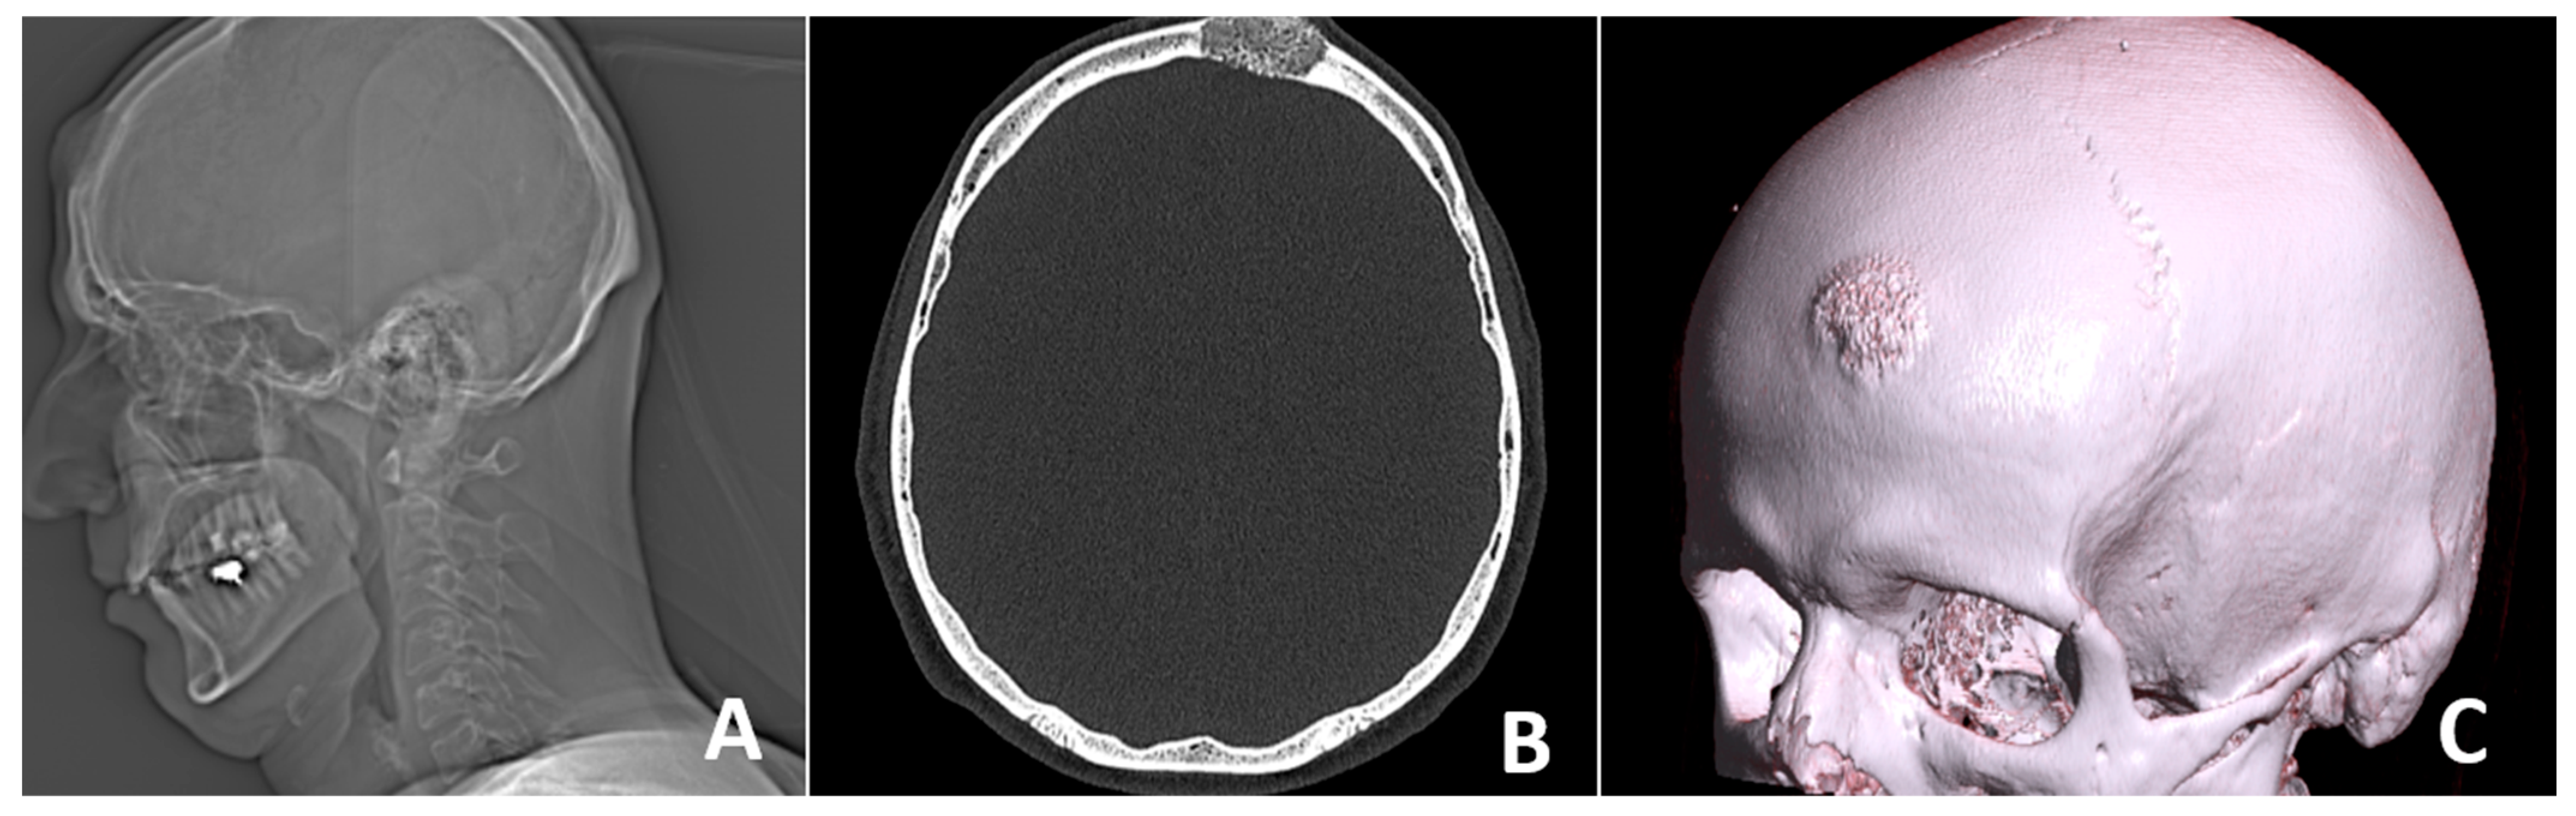

2. Case Report